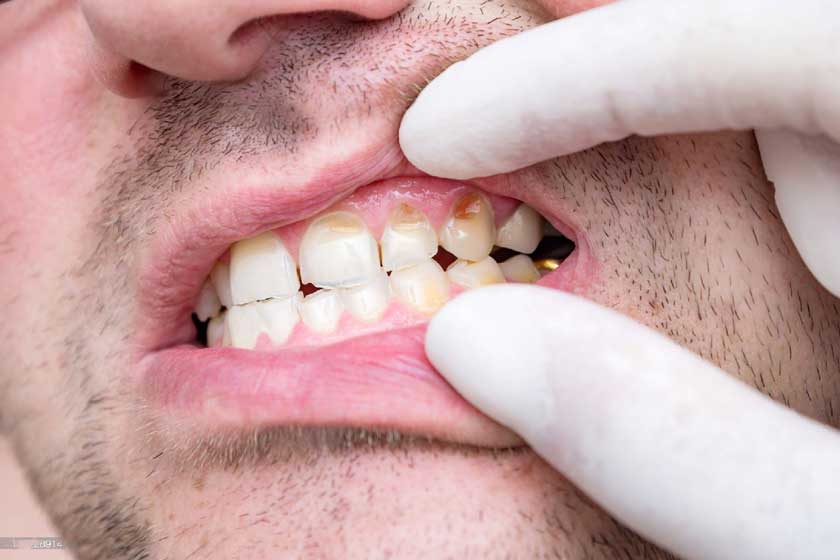

Biểu hiện đầu tiên của sâu răng là những vệt trắng đục và đốm đen li ti trên răng, đây là giai đoạn sâu men răng. Sau đó, sâu răng sẽ lan vào ngà răng gây cảm giác nhói, ê buốt mỗi khi có yếu tố kích thích như nhiệt độ nóng lạnh, đánh răng…

Cuối cùng sâu ăn vào tủy răng sẽ gây ra cảm giác đau nhức, nặng sẽ gây biến chứng viêm tủy, sưng mặt, đau lên tận đầu, áp-xe răng, viêm mô tế bào, nhiễm trùng máu…

Sâu răng ở người lớn